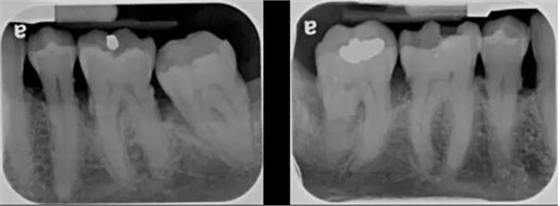

圖 3 診斷質(zhì)量欠佳的根尖片(原因:牙合 面顯示太多,說明 X 光片拍攝角度有問題,片子有變形)

要是碰巧根尖片沒達(dá)到這個(gè)標(biāo)準(zhǔn)呢?那要看這是解剖原因造成的(有些患者無法忍受口腔里置放片子,會有惡心反應(yīng);或是腭部弧度過小、平坦,片子無法平行于牙長軸),還是拍片技術(shù)原因造成的。如果是技術(shù)原因造成的,需要提高拍片技術(shù)。